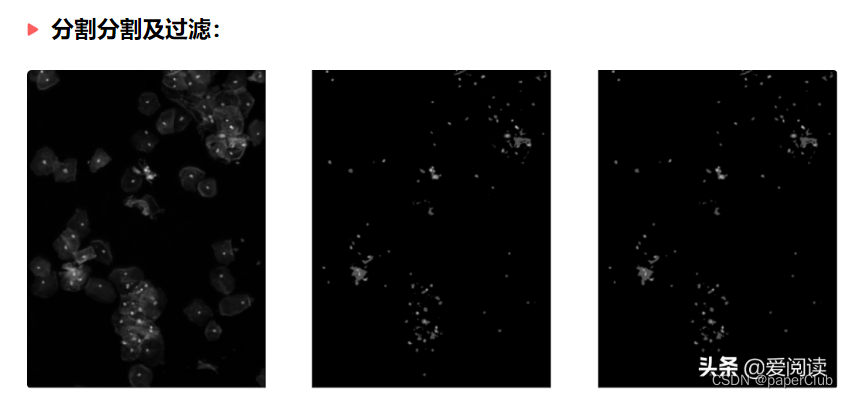

细胞区域初步分割结果:

_,bw_nucleus_s = cv2.threshold(img_s, 10, 255, cv2.THRESH_BINARY)

bw_nucleus = cv2.bitwise_and(bw_nucleus, bw_nucleus_s))

fig = plt.figure(figsize=(15,8))

plt.subplot(121),plt.imshow(bw_nucleus_s, 'gray') , plt.xticks([]),plt.yticks([])

plt.subplot(122),plt.imshow(bw_nucleus, 'gray'), plt.xticks([]),plt.yticks([])

plt.show()